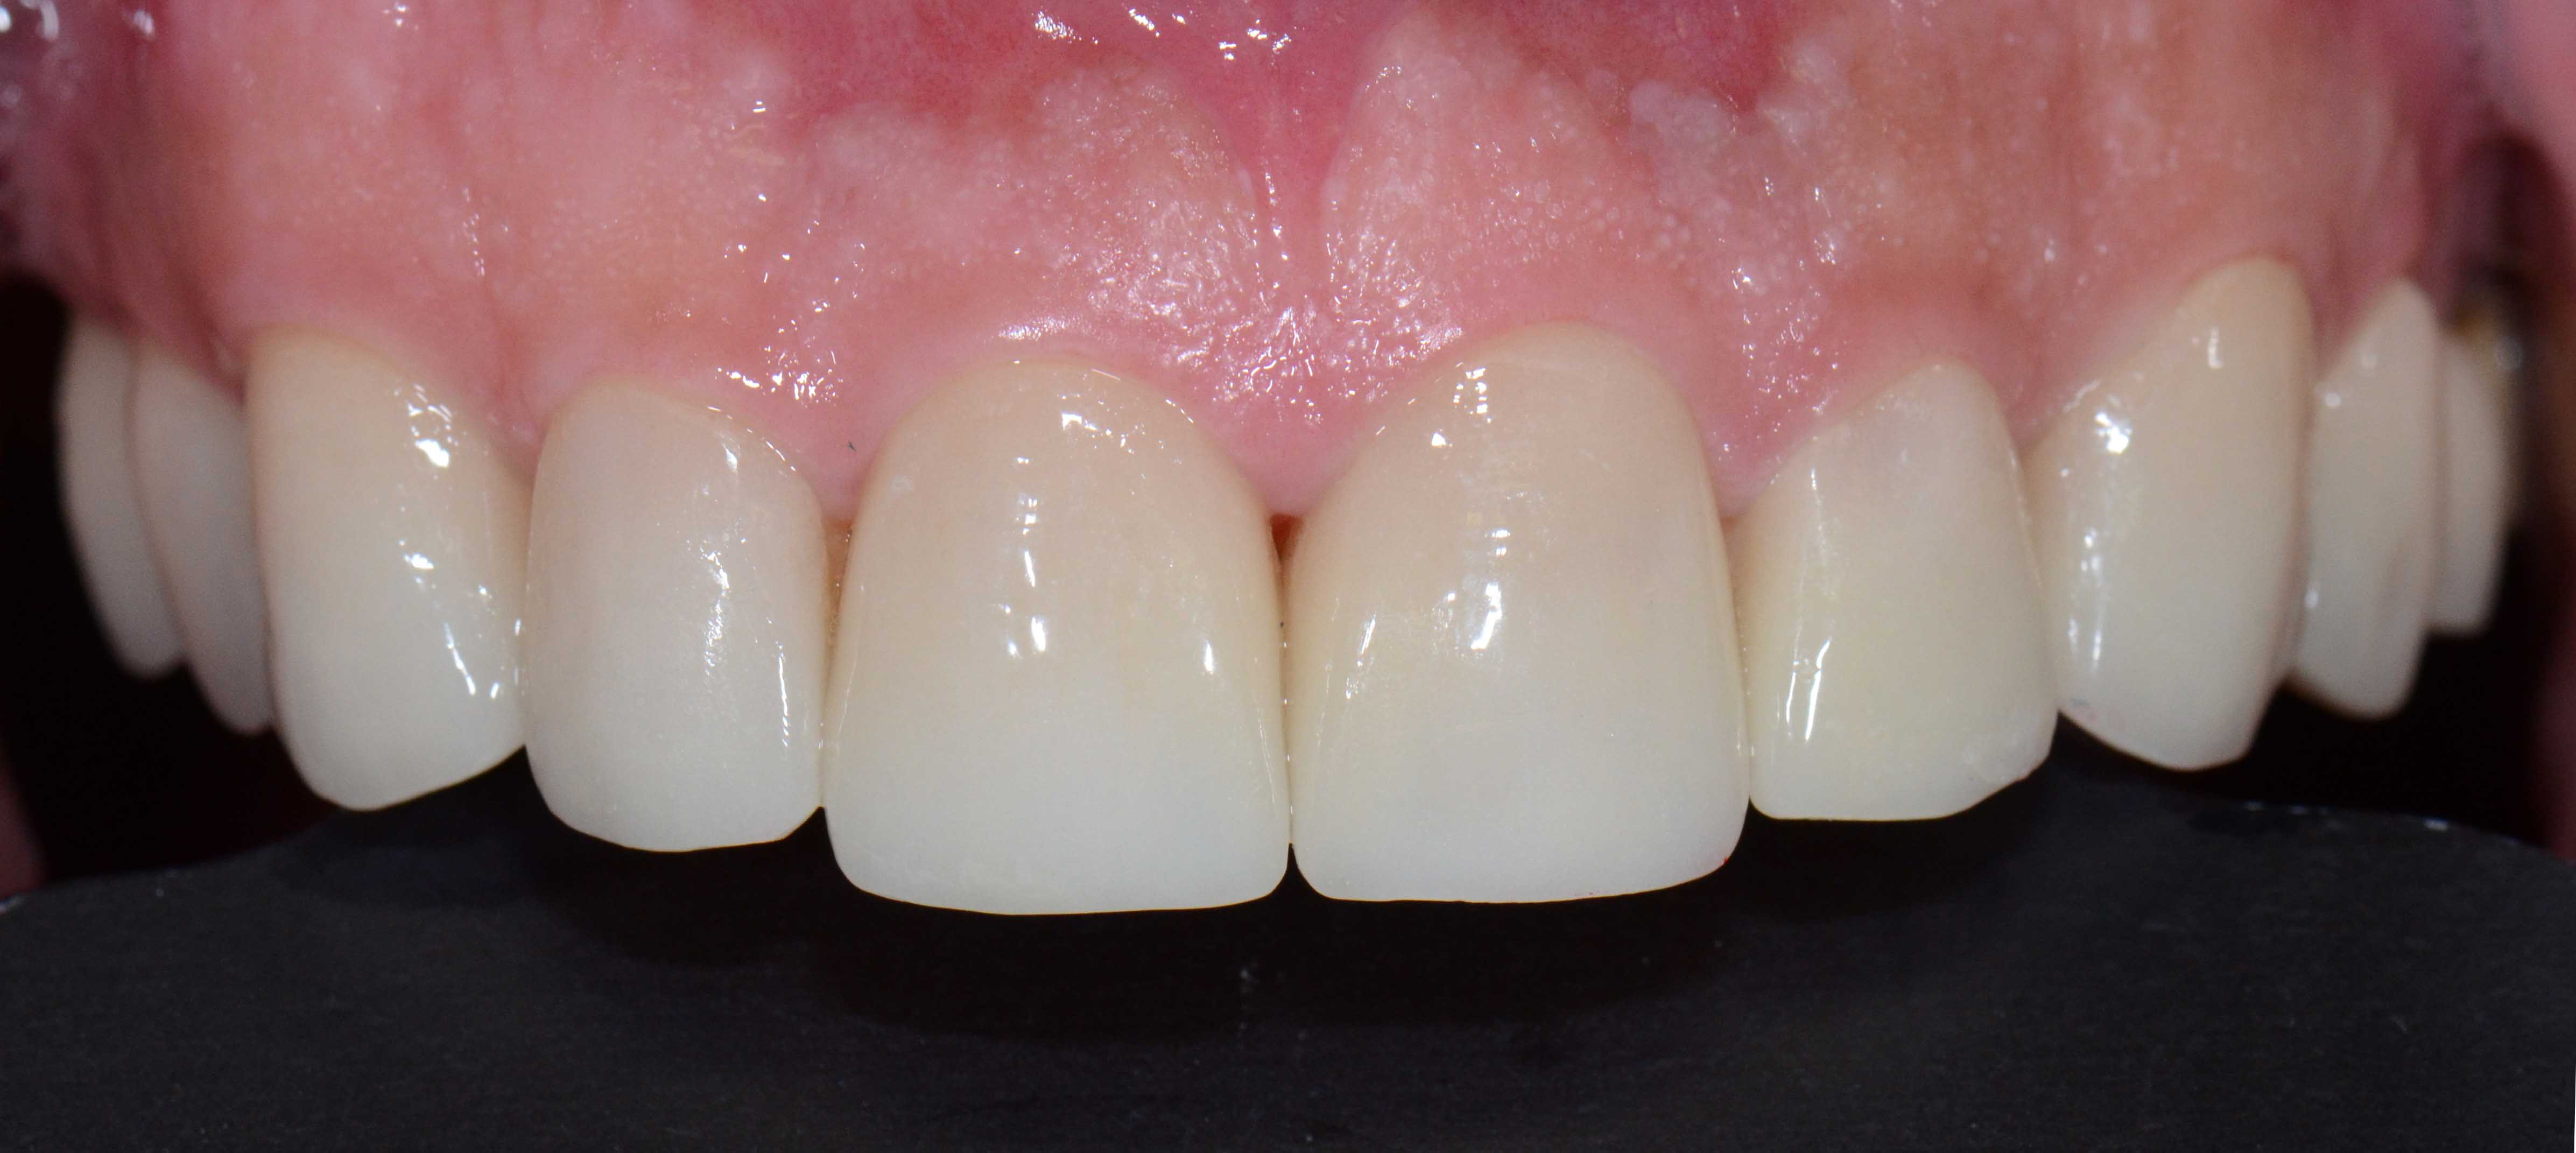

Alterações de Cor por Tetraciclinas

Reabilitação Estética com Coroas e Facetas Cerâmicas.

Problema Principal

Alterações de cor devido a utilização de Tetraciclinas em criança. Vários tratamentos feitos ao longa da vida para disfarçar o problema sem resultados satisfatórios.

Tratamento

Opção por recobrimento dentário com coroas nos dentes mais destruidos e de facetas naqueles menos atingidos evitando desgastes muito agressivos.